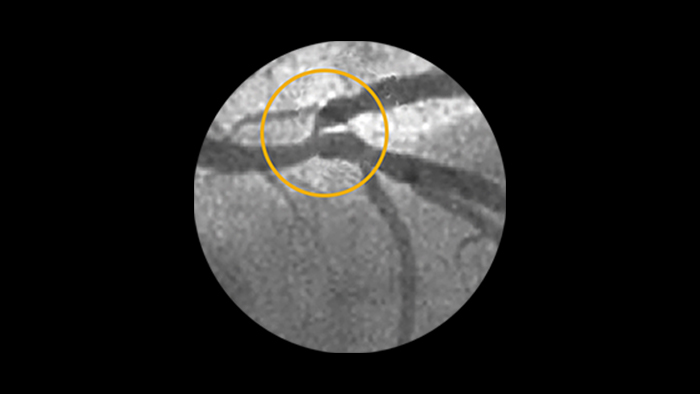

Calcified Lesions

Recent pooled analysis reported moderate to severe target lesion calcification in 32% of patients.6